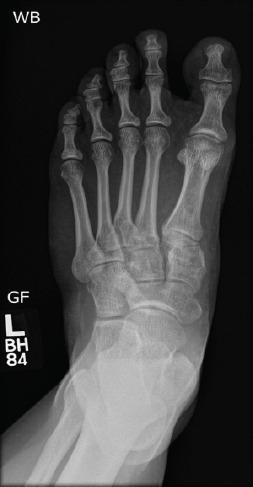

Various methods are used for open reduction and internal fixation of Lisfranc injuries, and each shows different post-treatment outcomes. Other than the common post-surgery problems in these patients, including possible non-anatomical reduction, implant loosening, breakage, and arthritis, most of these patients will undergo a second surgery for implant removal which itself might cause further complications. To reduce the need for re-operation, bio-degradable or bio-integrative implants can be promising; however, the short- and long-term outcomes have been scarcely investigated to date.

We followed up 10 adult patients who received bio-integrative screws for Lisfranc injuries. The patients were asked to fill out the patient-reported outcome measures (PROMs) surveys during one of the follow-up visits. We gathered variables including the type of injury, pain score, and PROMs including physical function (PF), pain interference, pain intensity, and depression. We evaluated the patients for wound dehiscence, non-union, and hardware failure. The median (interquartile range [IQR]) follow-up time of the patients in this study was 9 (4-11.5) months. Nine out of 10 patients with Lisfranc injuries who received bio-integrative screws showed improvements in their pain scores and started progressive weight-bearing. Among 3 patients who had sport-related Lisfranc injuries, 2 returned to play in <6 months, and one started side-to-side agility work in <3 months. The median (IQR) scores of PROMs representing PF, depression, physical health, mental health, pain interference, and pain intensity were 49.5 (30.1-61.9), 41 (41-49), 50.8 (39.2-57.7), 59 (48.9-63.7), 51.7 (41.6-72.6), and 43.5 (37.8-55.2), respectively.

多种方法用于Lisfranc损伤的切开复位内固定,每种方法都显示出不同的治疗后结果。除了这些患者常见的术后问题,包括可能的非解剖复位、植入物松动、断裂和关节炎外,这些患者中的大多数将接受二次手术取出植入物,而这本身可能会导致进一步的并发症。为了减少再次手术的需求,生物可降解或生物整合植入物可能很有前景;然而,迄今为止,对其短期和长期结果的研究很少。

我们对10例接受生物整合螺钉治疗Lisfranc损伤的成年患者进行了随访。要求患者在一次随访中填写患者报告的结局指标(PROMs)调查问卷。我们收集了包括损伤类型、疼痛评分以及PROMs(包括身体功能(PF)、疼痛干扰、疼痛强度和抑郁)等变量。我们评估了患者的伤口裂开、骨不连和内固定失败情况。本研究中患者的中位(四分位间距[IQR])随访时间为9(4 - 11.5)个月。10例接受生物整合螺钉治疗的Lisfranc损伤患者中有9例疼痛评分有所改善,并开始逐步负重。在3例与运动相关的Lisfranc损伤患者中,2例在6个月内恢复运动,1例在3个月内开始进行双侧敏捷性训练。代表PF、抑郁、身体健康、心理健康、疼痛干扰和疼痛强度的PROMs中位(IQR)评分分别为49.5(30.1 - 61.9)、41(41 - 49)、50.8(39.2 - 57.7)、59(48.9 - 63.7)、51.7(41.6 - 72.6)和43.5(37.8 - 55.2)。